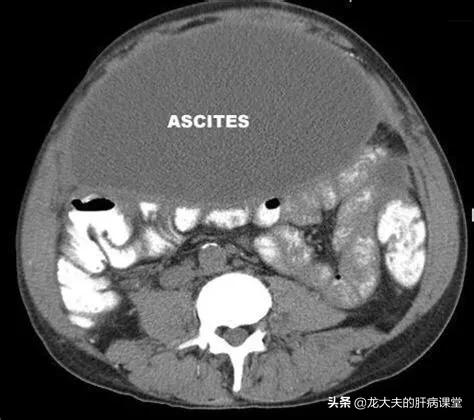

出现腹水的肝病,一般属于肝硬化失代偿期。肝硬化失代偿期的终末阶段,会伴有各种各样的并发症,不是说有腹水就可以确定是肝硬化晚期。这些并发症包括严重感染、肝性脑病和上消化道出血,等等。

腹水的治疗:腹水的治疗,包括抽腹水、利尿,以减轻压迫症状。同时,要使用抗感染药,针对可能的病原体,使用抗菌药或者抗真菌药等。

营养支持治疗:腹水的一个重要原因是白蛋白降低,白蛋白主要是肝细胞合成的。在肝功能减退到一定程度之后,白蛋白的合成减少,这个时候需要额外的补充白蛋白,可以利尿治疗。利尿也是要腹水治疗的重要措施之一。